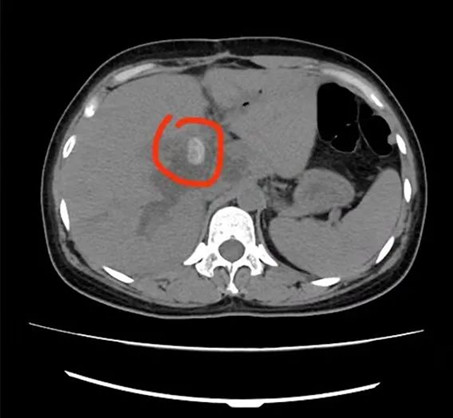

5分鐘后,楊林副主任便趕到急診科,這時腹部CT結(jié)果已經(jīng)出來:肝內(nèi)外膽管多發(fā)結(jié)石,肝內(nèi)外膽管擴張;膽囊切除后;肝門下緣胃大彎旁囊性病變伴高密度影。

綜合患者病情,楊林副主任認為其是典型的感染性休克;化膿性膽管炎;肝內(nèi)外膽管結(jié)石,如不立刻進行手術(shù),會出現(xiàn)嚴重的并發(fā)癥甚至危及生命。

術(shù)前

術(shù)后

據(jù)悉,術(shù)中共取出19顆“石子”?;颊哌M入重癥醫(yī)學科(ICU)觀察,隨后病情穩(wěn)定后轉(zhuǎn)入普外科病房繼續(xù)進行治療,目前患者病情穩(wěn)定,不日即可康復出院。